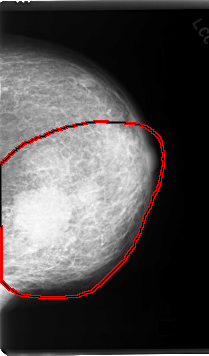

C_0055_1.LEFT_MLO

LEFT_MLO LINES 5944 PIXELS_PER_LINE 3704 BITS_PER_PIXEL 12 RESOLUTION 50 OVERLAY

FILE: C_0055_1.LEFT_MLO.OVERLAY

TOTAL_ABNORMALITIES 1

ABNORMALITY 1

LESION_TYPE CALCIFICATION TYPE PLEOMORPHIC DISTRIBUTION SEGMENTAL

ASSESSMENT 5

SUBTLETY 5

PATHOLOGY MALIGNANT

TOTAL_OUTLINES 1

BOUNDARY